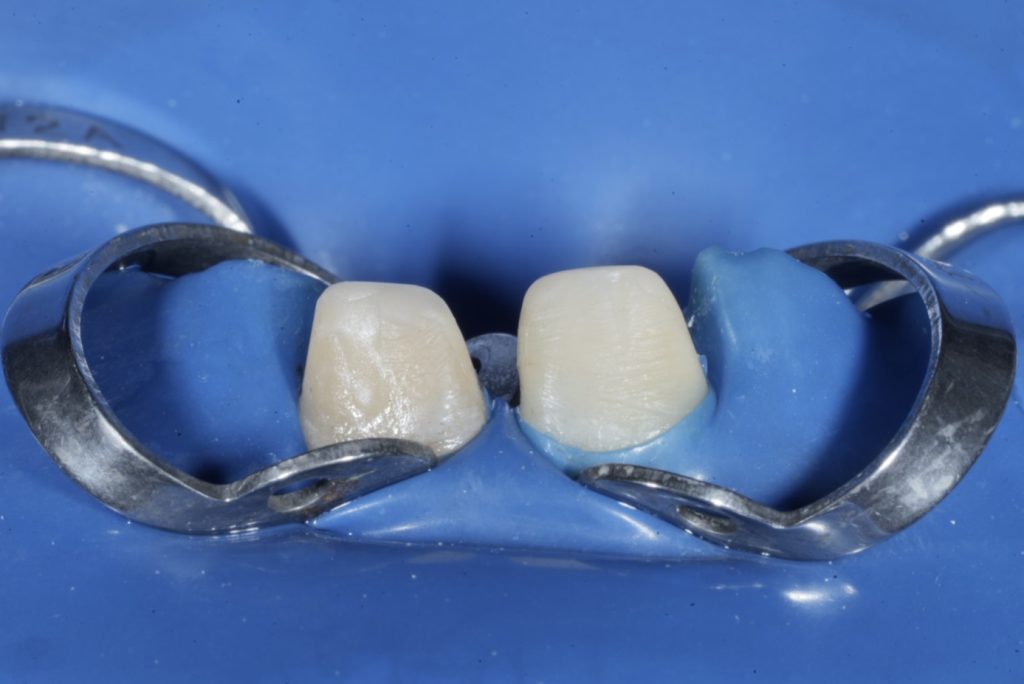

1 — Isolation and Access

Rubber-dam isolation (blue dam) was secured using W2A clamps for moisture control and soft-tissue protection (Fig 1-2).